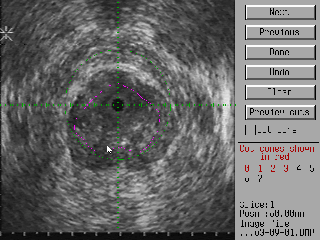

The display below is used by the surgeon to adjust the cutting cones. The computer starts by making each cone as long as possible, however the surgeon can fine-tune the cutting program by adjusting the cone lengths and turning on or off specific cones (the initial geometry specified by the surgeon may be such that some cones the computer generates more-or-less completely overlap other cones. A case in point is shown below. To save cutting time, the surgeon can shorten the right hand cone (marked green). Click here or on the image for a larger version.